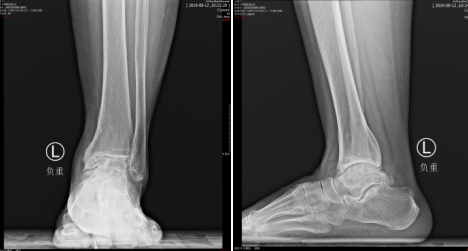

20年前,刚刚40岁的王大妈发觉双侧踝关节疼痛,随着年龄增长,疼痛加剧,不能长时间负重行走,到了今年走上200米双脚脚踝处便疼痛难忍,得坐下来缓解。王大妈多方打听,来到betway在线登陆求诊,足踝科曹广超主任接诊了王大妈,检查之后安排做CT,结果显示:患者双侧踝关节炎,左距下关节炎。

“患者是位老年女性,20年前脚踝有过扭伤,后期疼痛不断加重,近来不能长时间走路。到咱们医院一检查,双侧踝关节炎,左侧的距下关节也出现病变,患者想改善症状,我们把病人的检查结果发给俞教授看,一起进行评估,选择了一种最适合患者的治疗,因为目前左侧比较重,就把左侧踝关节距下关节都做了融合,把后足的跟骨、距骨、胫骨钉死,把脚踝放正,以后她的走路就会好很多。”参与手术的赵亮医生说。